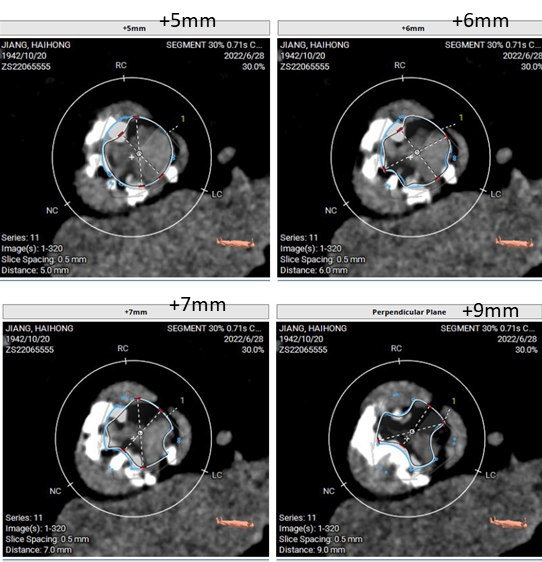

术前CT

术前CT

术前CT